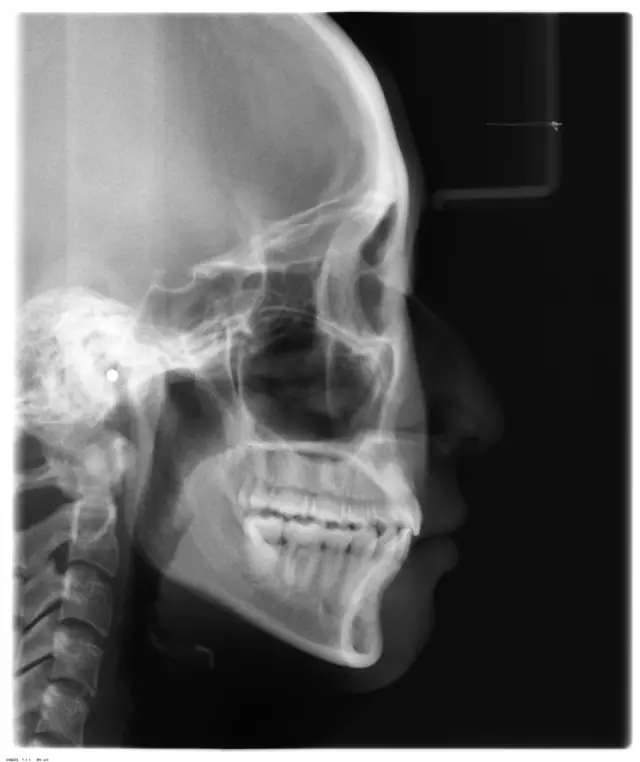

Damon 病例分享:安氏 II 類二分類露齦笑的矯治(董一磊)